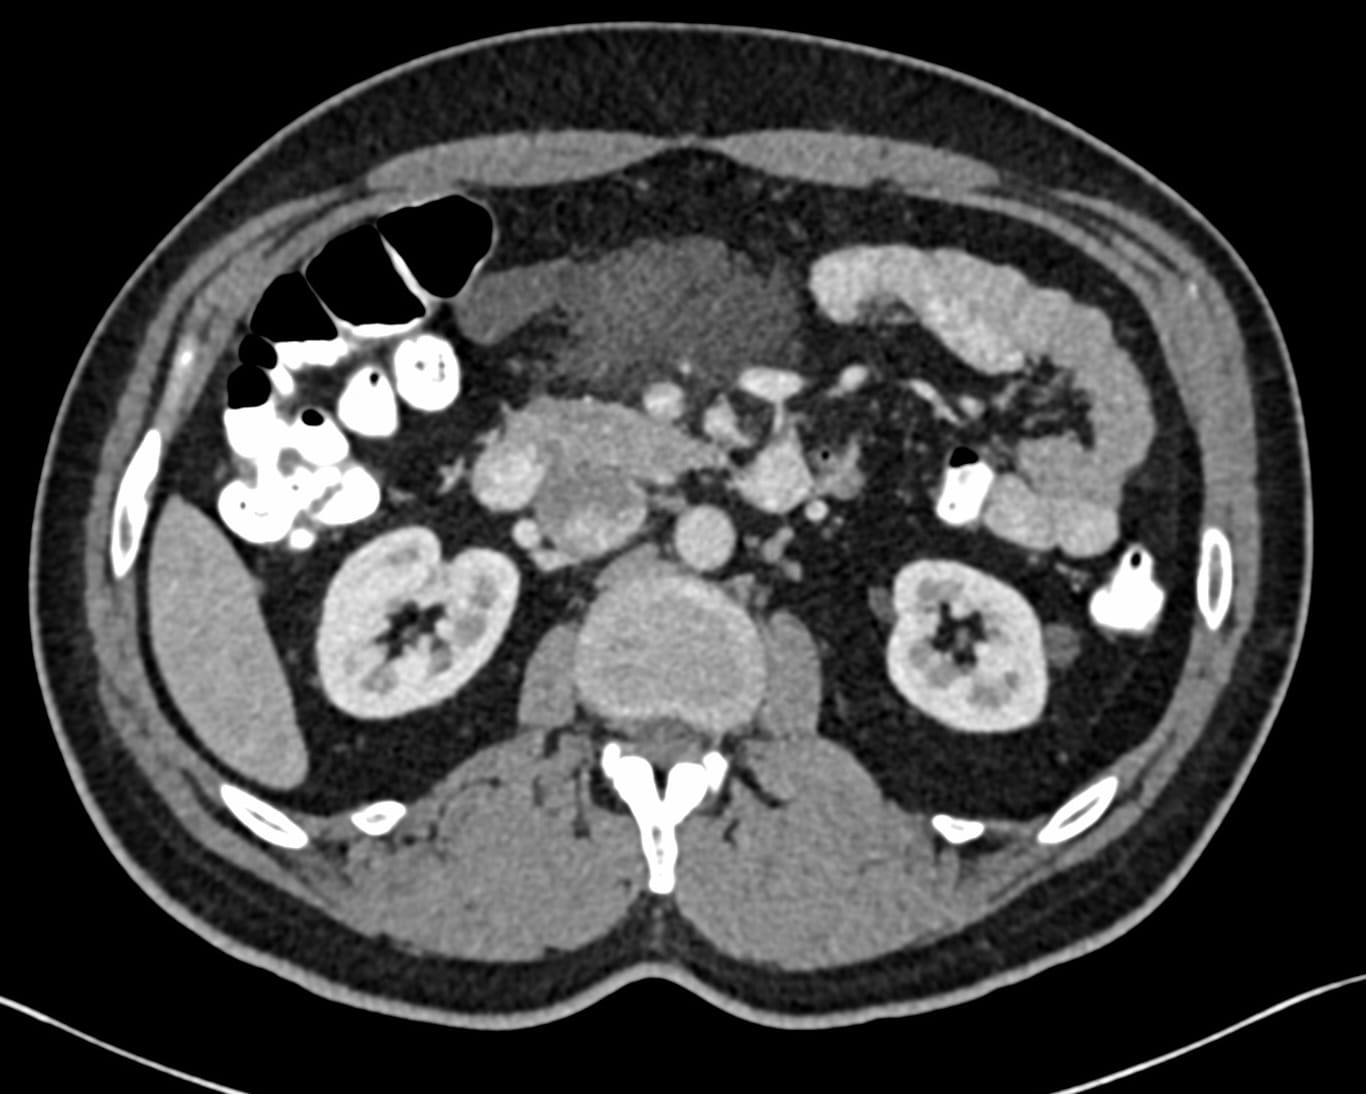

A 54-years old with a mesenteric mass presented for a biopsy - the mass was unchanged over 6 months.

Though, this was likely a lymphatic cyst, the surgeon wanted a biopsy, because one of the earlier reports had raised the possibility of lymphoma.

The biopsy was performed with an 18G BARD coaxial gun. Milky fluid was aspirated, which confirmed the diagnosis.